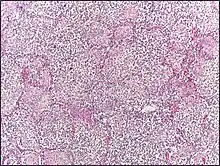

- Congestion in the first 24 hours: This stage is characterized histologically by vascular engorgement, intra-alveolar fluid, small numbers of neutrophils, often numerous bacteria. Grossly, the lung is heavy and hyperemic.

- Red hepatization or consolidation: Vascular congestion persists, with extravasation of red blood cells into alveolar spaces, along with increased numbers of neutrophils and fibrin. The filling of airspaces by the exudate leads to a gross appearance of solidification, or consolidation, of the alveolar parenchyma. This appearance has been likened to that of the liver, hence the term "hepatization".

- Grey hepatization: Red blood cells disintegrate, with persistence of the neutrophils and fibrin. The alveoli still appear consolidated, but grossly the color is paler and the cut surface is drier. This is when death typically occurs in severe cases.